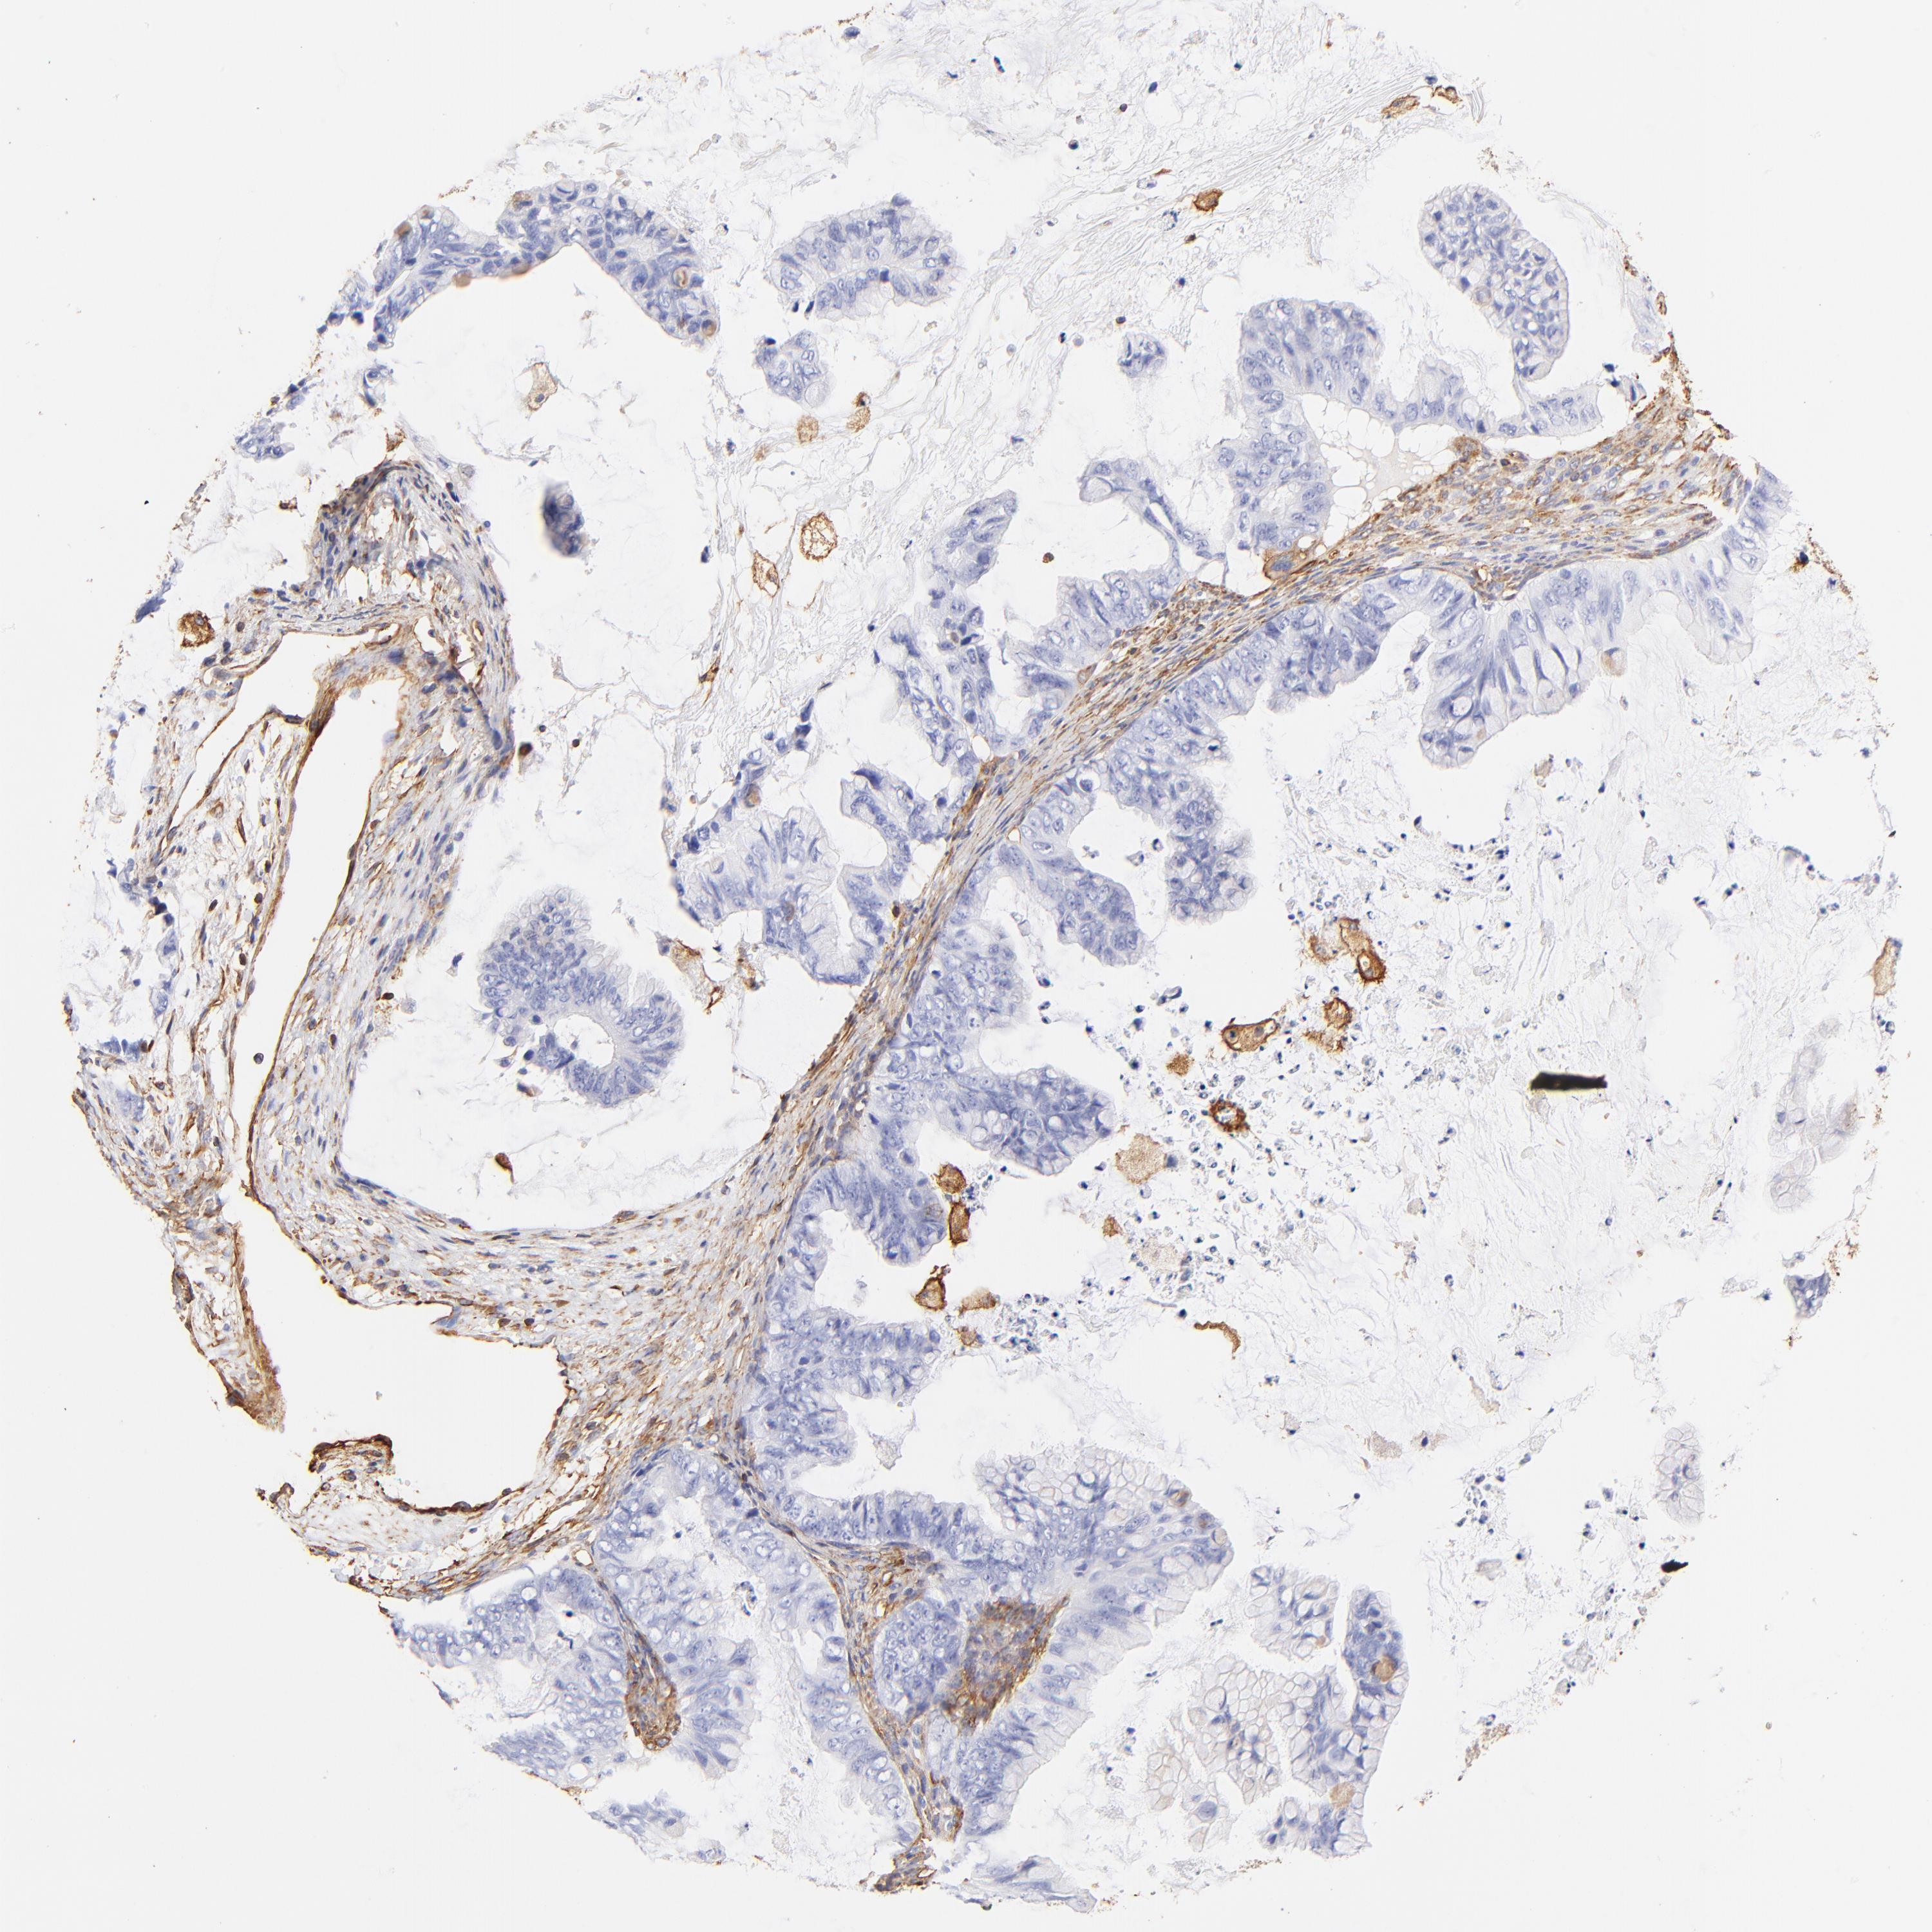

OVARIAN CANCER - Protein expressioni

A mouse-over function shows sample information and annotation data. Click on an image to view it in a full screen mode. Samples can be filtered based on level of antibody staining by selecting one or several of the following categories: high, medium, low and not detected. The assay and annotation is described here.

Note that samples used for immunohistochemistry by the Human Protein Atlas do not correspond to samples in the TCGA dataset.

Antibody stainingi

Antibody staining in the annotated cell types in the current human tissue is reported as not detected, low, medium, or high, based on conventional immunohistochemistry profiling in selected tissues. This score is based on the combination of the staining intensity and fraction of stained cells.

Each image is clickable and will lead to virtual microscopy that enables deeper exploration of all samples and also displays staining intensity scores, fraction scores and subcellular localization as well as patient and tissue information for each sample.

Antibody HPA001115

Antibody HPA002925

Antibody CAB000356

Cystadenocarcinoma, mucinous, NOS

Carcinoma, endometroid

Cystadenocarcinoma, serous, NOS